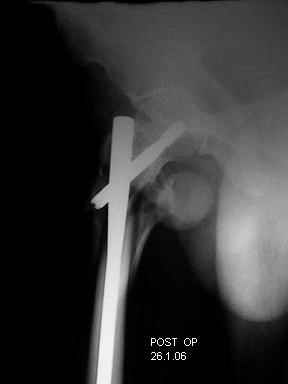

I choose Long Gamma Nailing and did it on 24.1.2006.

Now posting the post op x-rays for all of yours comments please. Don't hesitate to criticize me.

Congratulations. Virtually perfect. What reduction technique did you use? Looks like still traction table? To cavil to at least something looks like reduction is in microscopic varus - comparative x-rays can clear this - though only for academic interest with no clinical significance. Did you insert distal screws?